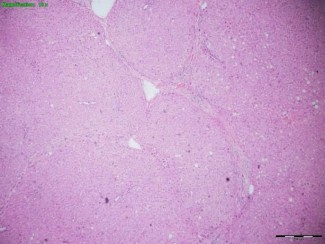

Hình 2.9. Tổn thương gan 3/6 theo Ishak (BN N20-0204706)